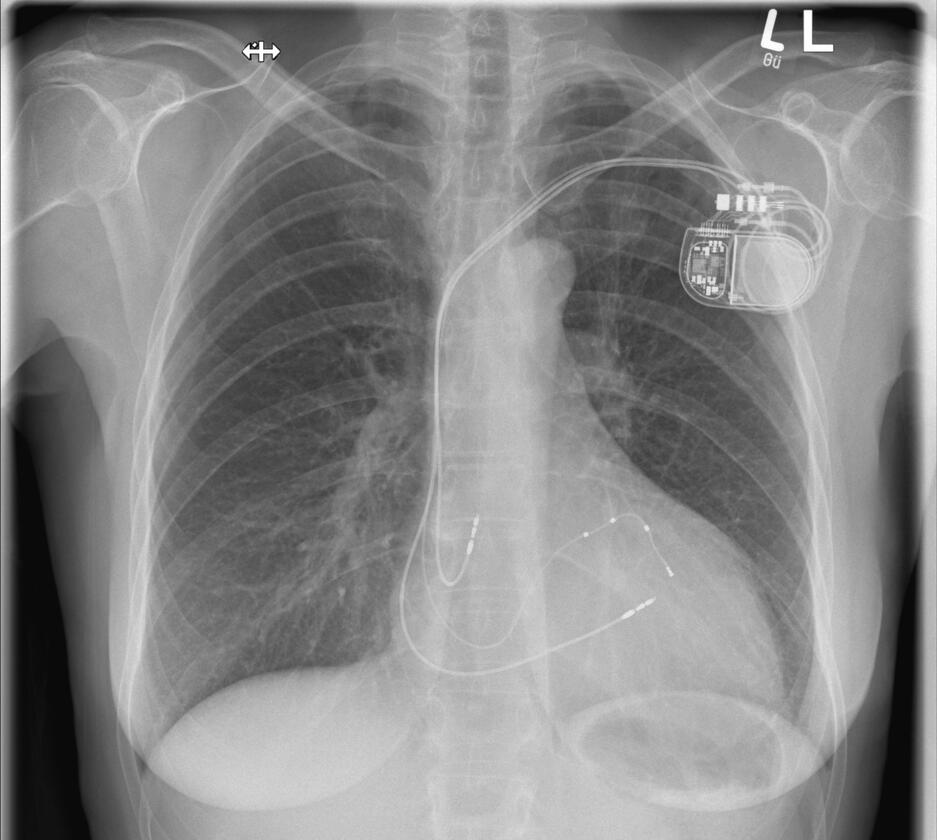

Wenn das Herz zu langsam schlägt, dann spricht man von einer Bradykardie. Diese ist meistens behandlungsbedürftig, denn sie kann zu Ohnmachtsanfällen (Synkopen) und im schlimmsten Fall zu einem Herzstillstand führen. Wenn sich keine behebbare Ursache finden lässt, ist die Implantation eines Herzschrittmachers die Therapie der Wahl. Der Schrittmacher regt den Herzmuskel mit leichten nicht spürbaren elektrischen Impulsen zum regelmäßigen Schlagen an. Der Herzschrittmacher wird in der Regel im Brustbereich unterhalb des Schlüsselbeines eingesetzt. Der kleine Eingriff erfolgt unter lokaler Betäubung während eines kurzen stationären Aufenthaltes oder auch ambulant. In unserer Klinik werden alle gängigen Systeme implantiert. Gerne informieren wir Sie in unserer Sprechstunde über weitere Einzelheiten. Hier erfolgt auf Wunsch auch die Nachsorge der implantierten Geräte (Sprechstunde).

Defibrillator

Die Implantation eines Defibrillators (ICD) erfolgt in der Regel bei einem erhöhten Risiko für gefährliche Herzrhythmusstörungen oder nach einem überlebten plötzlichen Herztod (SCD). Ein elektrischer Schock sorgt beim Auftreten einer entsprechenden Rhythmusstörung dafür, dass ein aus dem Takt geratenes Herz wieder richtig schlägt und die lebensbedrohliche Situation beendet wird. Die allermeisten Defibrillatoren haben zusätzlich die Funktion eines Herzschrittmachers. Ähnlich wie ein Herzschrittmacher wird das ICD-Gerät im Brustbereich unterhalb des Schlüsselbeines unter lokaler Betäubung eingesetzt. In unserer Klinik werden alle gängigen Systeme implantiert. Gerne informieren wir Sie in unserer Sprechstunde über weitere Einzelheiten. Hier erfolgt auf Wunsch auch die Nachsorge der implantierten Geräte (Sprechstunde).

Bei einer Herzmuskelschwäche pumpt der Herzmuskel häufig nicht mehr synchron. Aus diesem Grund kann es sinnvoll sein, diese „Asynchronie“ durch die Implantation zusätzlicher Stimulationssonden wieder zu beheben. Diese Sonden können die linke Herzkammer, aber auch direkt das Reizleitungssystem stimulieren. Eine solche kardiale Resynchronisationstherapie kann als reine Herzschrittmacherimplantation, aber auch in Kombination mit einem Defibrillator erfolgen. Grundsätzlich läuft die Operation wie die Implantation eines Herzschrittmachers ab, kann jedoch aufgrund der zusätzlichen Sonde(n) etwas länger dauern.